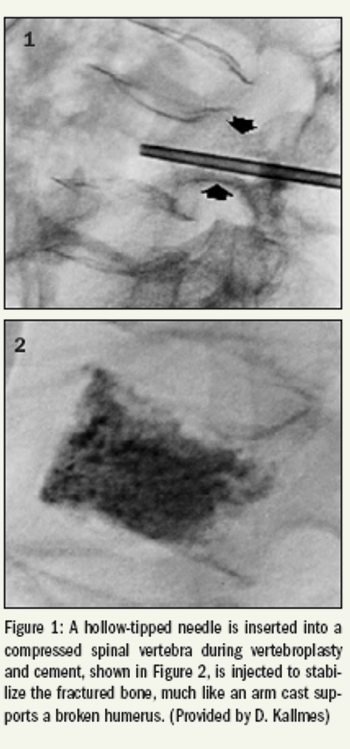

Interventional radiologists are coming to grips with the implications of two groundbreaking clinical trials indicating that vertebroplasty relieves pain from osteoporotic vertebral fractures no better than a sham version of the procedure.